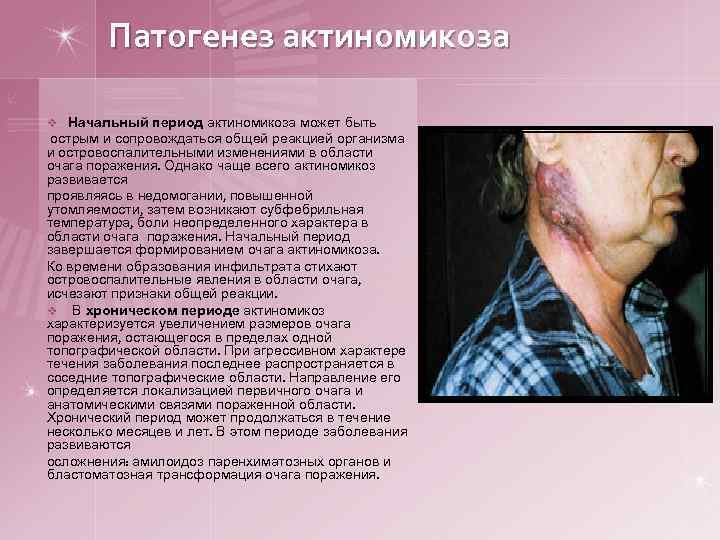

Патогенез актиномикоза v Начальный период актиномикоза может быть острым и сопровождаться общей реакцией организма и островоспалительными изменениями в области очага поражения. Однако чаще всего актиномикоз развивается проявляясь в недомогании, повышенной утомляемости, затем возникают субфебрильная температура, боли неопределенного характера в области очага поражения. Начальный период завершается формированием очага актиномикоза. Ко времени образования инфильтрата стихают островоспалительные явления в области очага, исчезают признаки общей реакции. v В хроническом периоде актиномикоз характеризуется увеличением размеров очага поражения, остающегося в пределах одной топографической области. При агрессивном характере течения заболевания последнее распространяется в соседние топографические области. Направление его определяется локализацией первичного очага и анатомическими связями пораженной области. Хронический период может продолжаться в течение несколько месяцев и лет. В этом периоде заболевания развиваются осложнения: амилоидоз паренхиматозных органов и бластоматозная трансформация очага поражения.